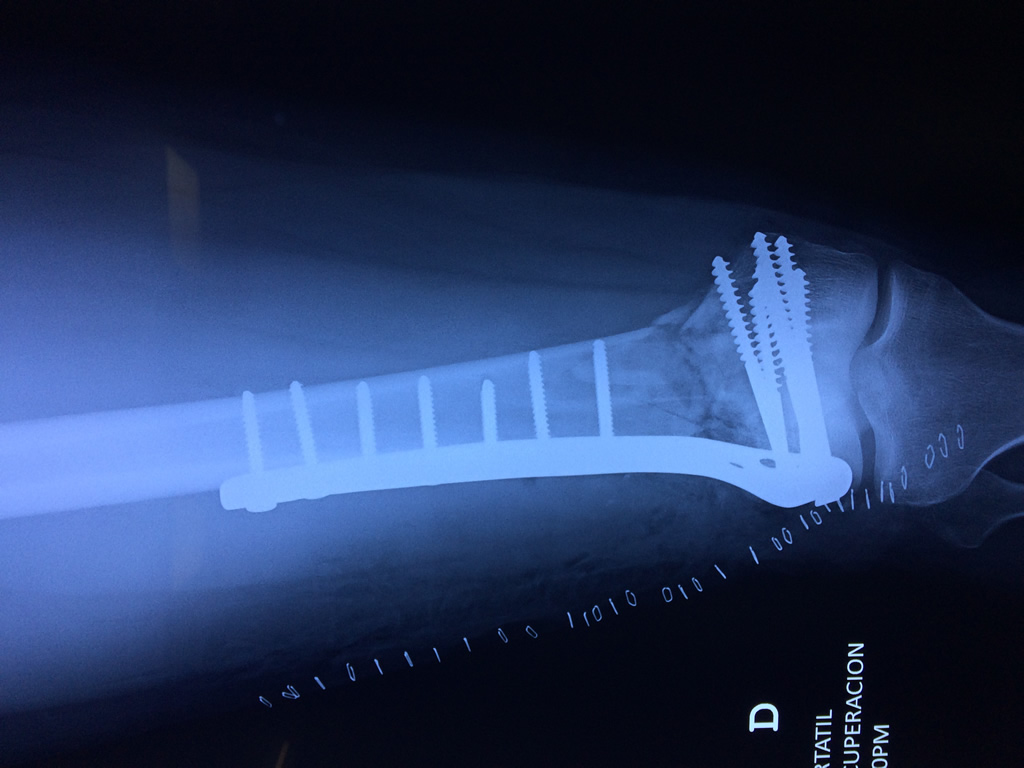

Cirugía de Cadera

El fémur es el hueso del muslo, el segundo segmento del miembro inferior. Es el hueso más largo, fuerte y voluminoso del cuerpo humano.